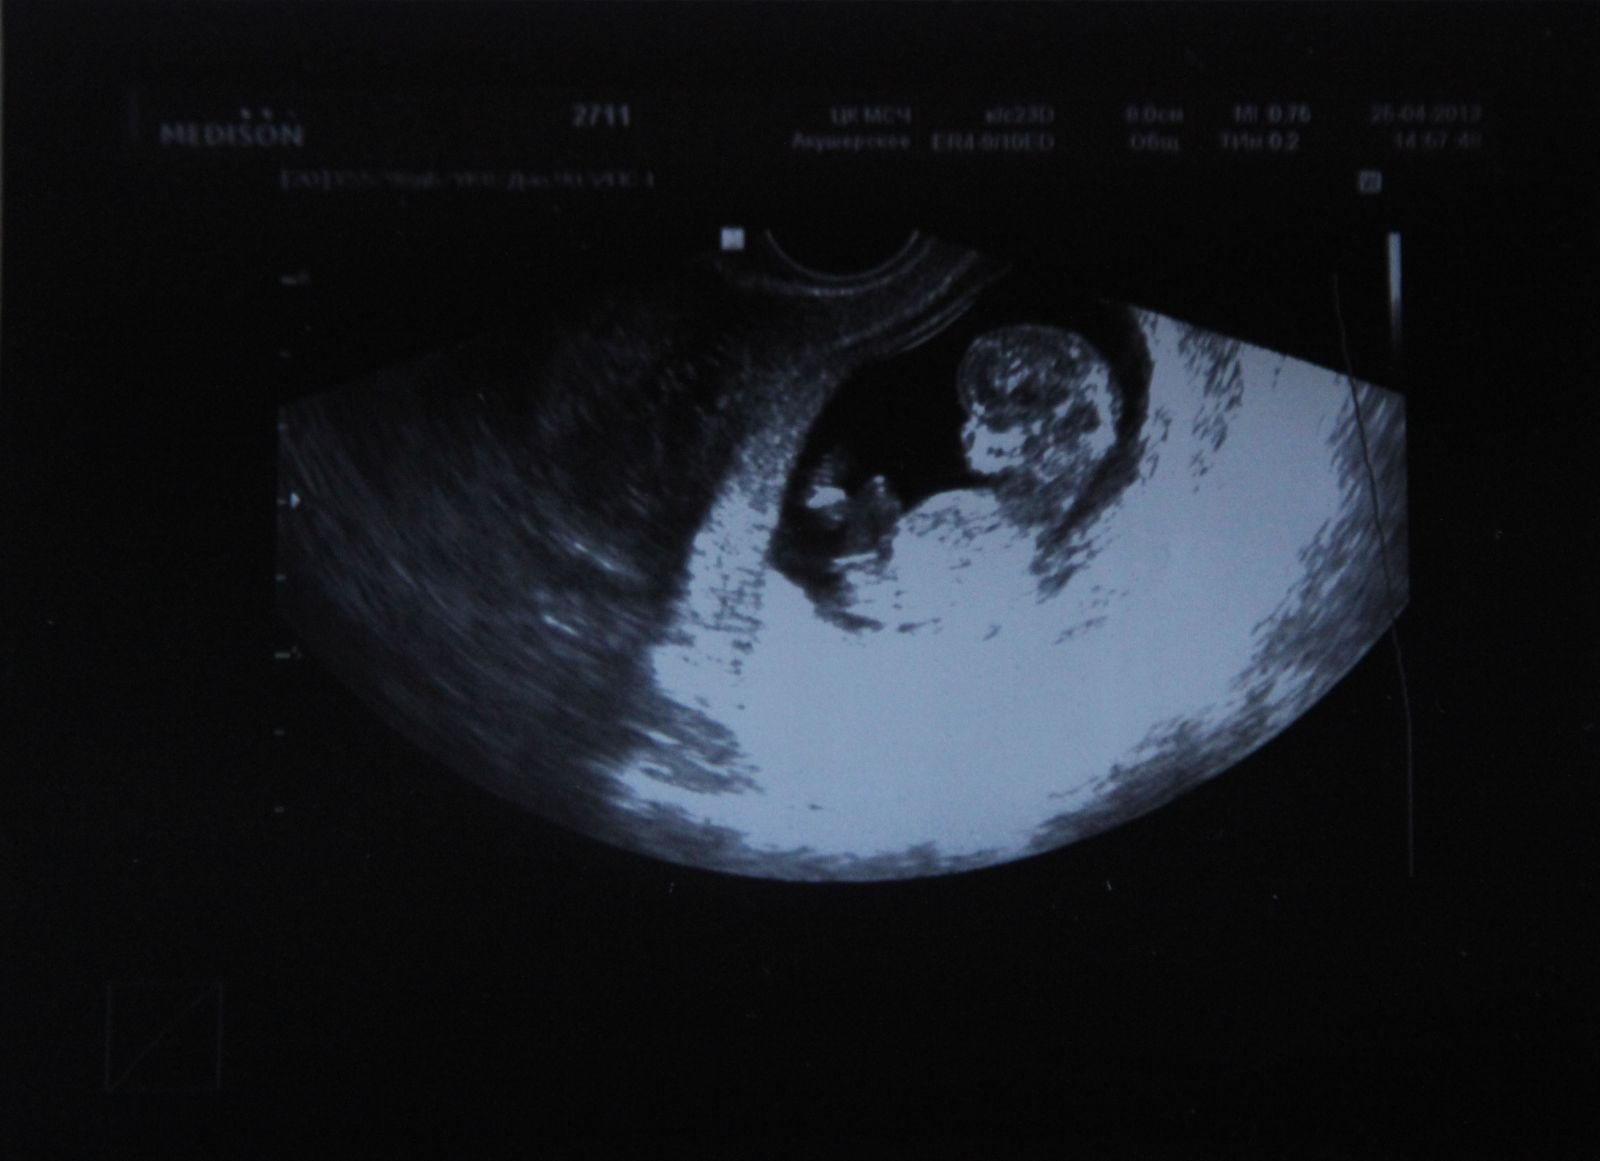

Хотя пока еще рано говорить о половой принадлежности ребенка на узи фото, уже можно увидеть формирование его черт лица. Глаза, нос, губы - все более четко проглядывается на узи снимках.

На каждом этапе беременности узи фотографии играют важную роль в мониторинге здоровья и развития ребенка. Они позволяют нам увидеть его рост, движения и формирование черт лица. Благодаря узи фото мы можем сопровождать малыша в его путешествии в мире материнства.